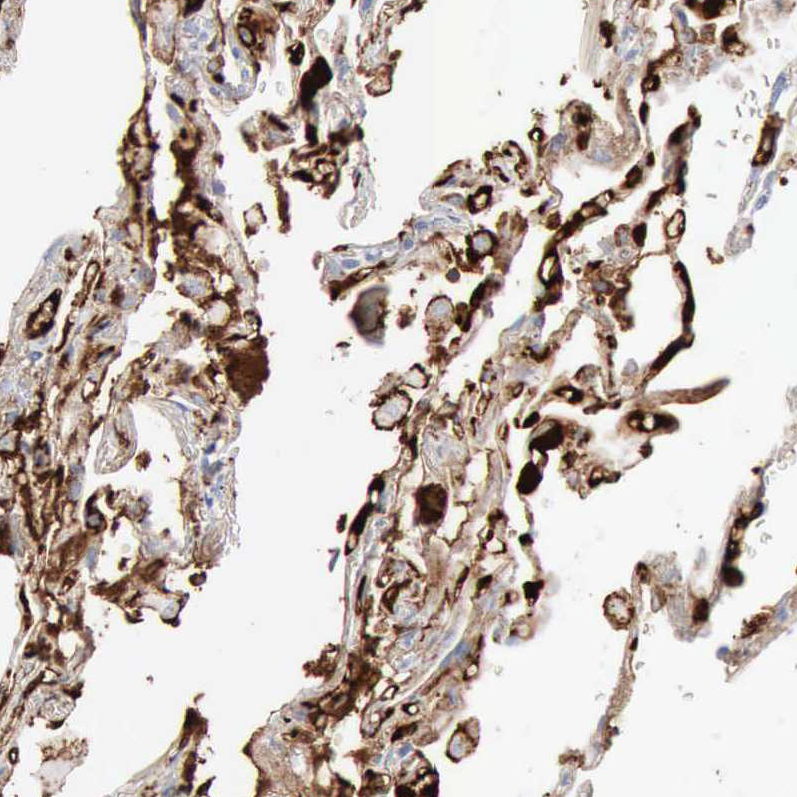

Immunohistochemical staining of human colon, kidney, liver and lung using Anti-C4BPA antibody HPA000926 (A) shows similar protein distribution across tissues to independent antibody HPA001578 (B).